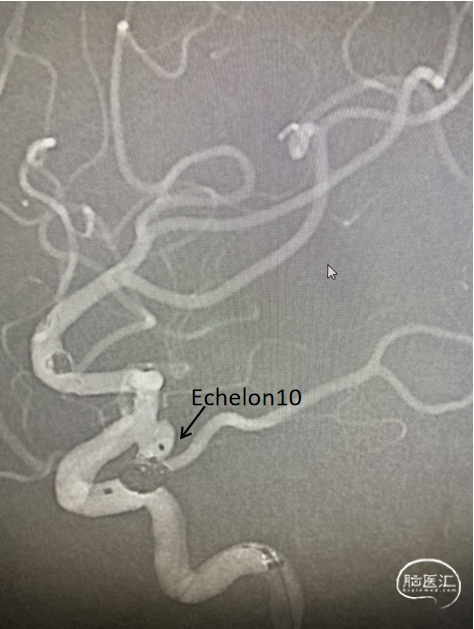

工作位+路图下Synchro-0.014in×200cm微导丝携带PROWLER SELECT PLUS微导管送至右侧大脑中动脉M2段远端,微导丝携带Echelon-10微导管送至M1段动脉瘤体内。经PROWLER SELECT PLUS微导管释放ENTERPRISE2 4.0mm×16mm,覆盖瘤颈,经Echelon依次填入强生ORBIT GALAXY 3mm×6cm弹簧圈成篮,继续填入ev3 2.5mm×6cm,1mm×2cm,1mm×1cm弹簧圈,造影示M1段动脉瘤填塞完全,造影剂滞留。

调整工作位角度,路图下Synchro0.014×200cmm微导丝携带SL-10微导管送至右侧颈内动脉,再用微导丝携带Echelon-10微导管送至C7动脉瘤瘤体内,经Echelon-10半释放强生ORBIT GALAXY 3mm×8cm弹簧圈,经SL-10释放Neuroform Altas 4.0mm×21mm支架,覆盖瘤颈,继续填塞第一枚弹簧圈,造影示支架位置满意,继续填塞强生ORBIT GALAXY 2mm×6cm弹簧圈,ev3 1mm×3cm,1mm×2cm弹簧圈,复查造影示动脉瘤栓塞致密,载瘤动脉通畅,复查颅内正侧位造影右侧颈内动脉、大脑前动脉、大脑中动脉显影良好。

路图下Synchro0.014×200cm微导丝携带PROWLER SELECT PLUS微导管送至右侧大脑中动脉M2段远端,微导丝携带Echelon-10微导管送至M1段动脉瘤体内。

经PROWLER SELECT PLUS微导管释放ENTERPRISE2 4.0mm×16mm,覆盖瘤颈,经Echelon依次填入强生ORBIT GALAXY 3mm×6cm弹簧圈成篮,继续填入ev3 2.5mm×6cm,1mm×2cm,1mm×1cm弹簧圈,造影示M1段动脉瘤填塞完全,造影剂滞留。

路图下Synchro0.014×200cmm微导丝携带SL-10微导管送至右侧颈内动脉,再用微导丝携带Echelon-10微导管送至C7动脉瘤瘤体内,经Echelon-10半释放强生ORBIT GALAXY 3mm×8cm弹簧圈,经SL-10释放Neuroform Altas 4.0mm×21mm支架,覆盖瘤颈。

造影示支架位置满意,继续填塞强生ORBIT GALAXY 2mm×6cm弹簧圈,ev3 1mm×3cm,1mm×2cm弹簧圈,复查造影示动脉瘤栓塞致密,载瘤动脉通畅。